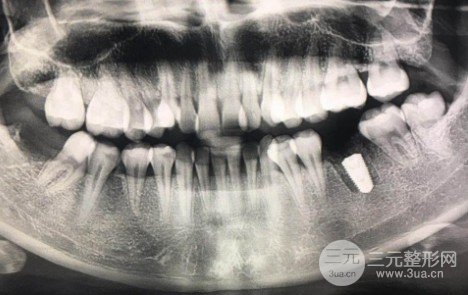

簡(jiǎn)單說(shuō)一下我的牙齒:今年20歲大二,高中時(shí)候因?yàn)榫徑獠环e極(完全沒(méi)有及時(shí)就醫(yī))壞了??偸峭现辉敢鈸Q敷料導(dǎo)致緩解結(jié)束時(shí)牙齒很脆,然后因?yàn)槌詵|西而裂開(kāi)。牙齒像中間的碗一樣碎了,不需要緩解,就在19年暑假拿出來(lái)了,拔完牙半年后去醫(yī)院了。種植牙的相關(guān)啊,也在網(wǎng)上學(xué)到很多理論知識(shí),我去頭一家,這個(gè)大夫甚至跟我說(shuō)還不錯(cuò)。但是照完之后發(fā)現(xiàn)骨量不夠!我從來(lái)沒(méi)想過(guò),因?yàn)楣橇烤拖穹N樹(shù)里的土,我連土都不夠!經(jīng)過(guò)三家醫(yī)院面對(duì)面診斷,結(jié)果是骨量不足,需要植骨,手術(shù)難度、風(fēng)險(xiǎn)、價(jià)格都上去了。當(dāng)時(shí)整個(gè)下午還是很郁悶,為什么大家都正常做了,我還要去做額外的一次手術(shù)?但每個(gè)人自身情況不同,術(shù)前面診和計(jì)劃尤為重要,于是去了同濟(jì)口腔醫(yī)院。